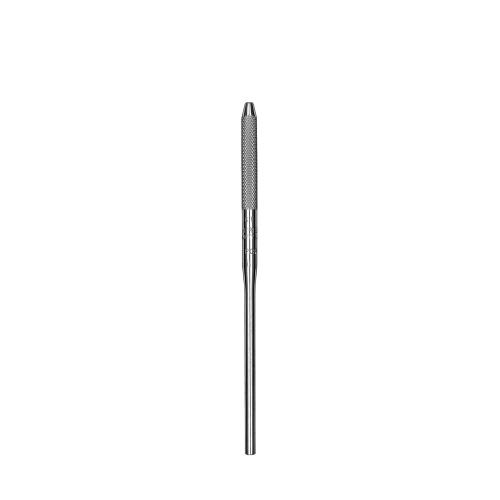

Sonde paro Novatech #NT15 Qulix 1-2-3-....-13-14-15

Sonde paro Novatech #NT15 Qulix 1-2-3-....-13-14-15

Sonde paro Novatech #NT15 Qulix 1-2-3-....-13-14-15

Sonde paro Novatech #NT15 Qulix 1-2-3-....-13-14-15

PCPNT15

PCPNT15

Novatech, color-coded probe.

Unique right angle design for improved adaptability in posterior regions.